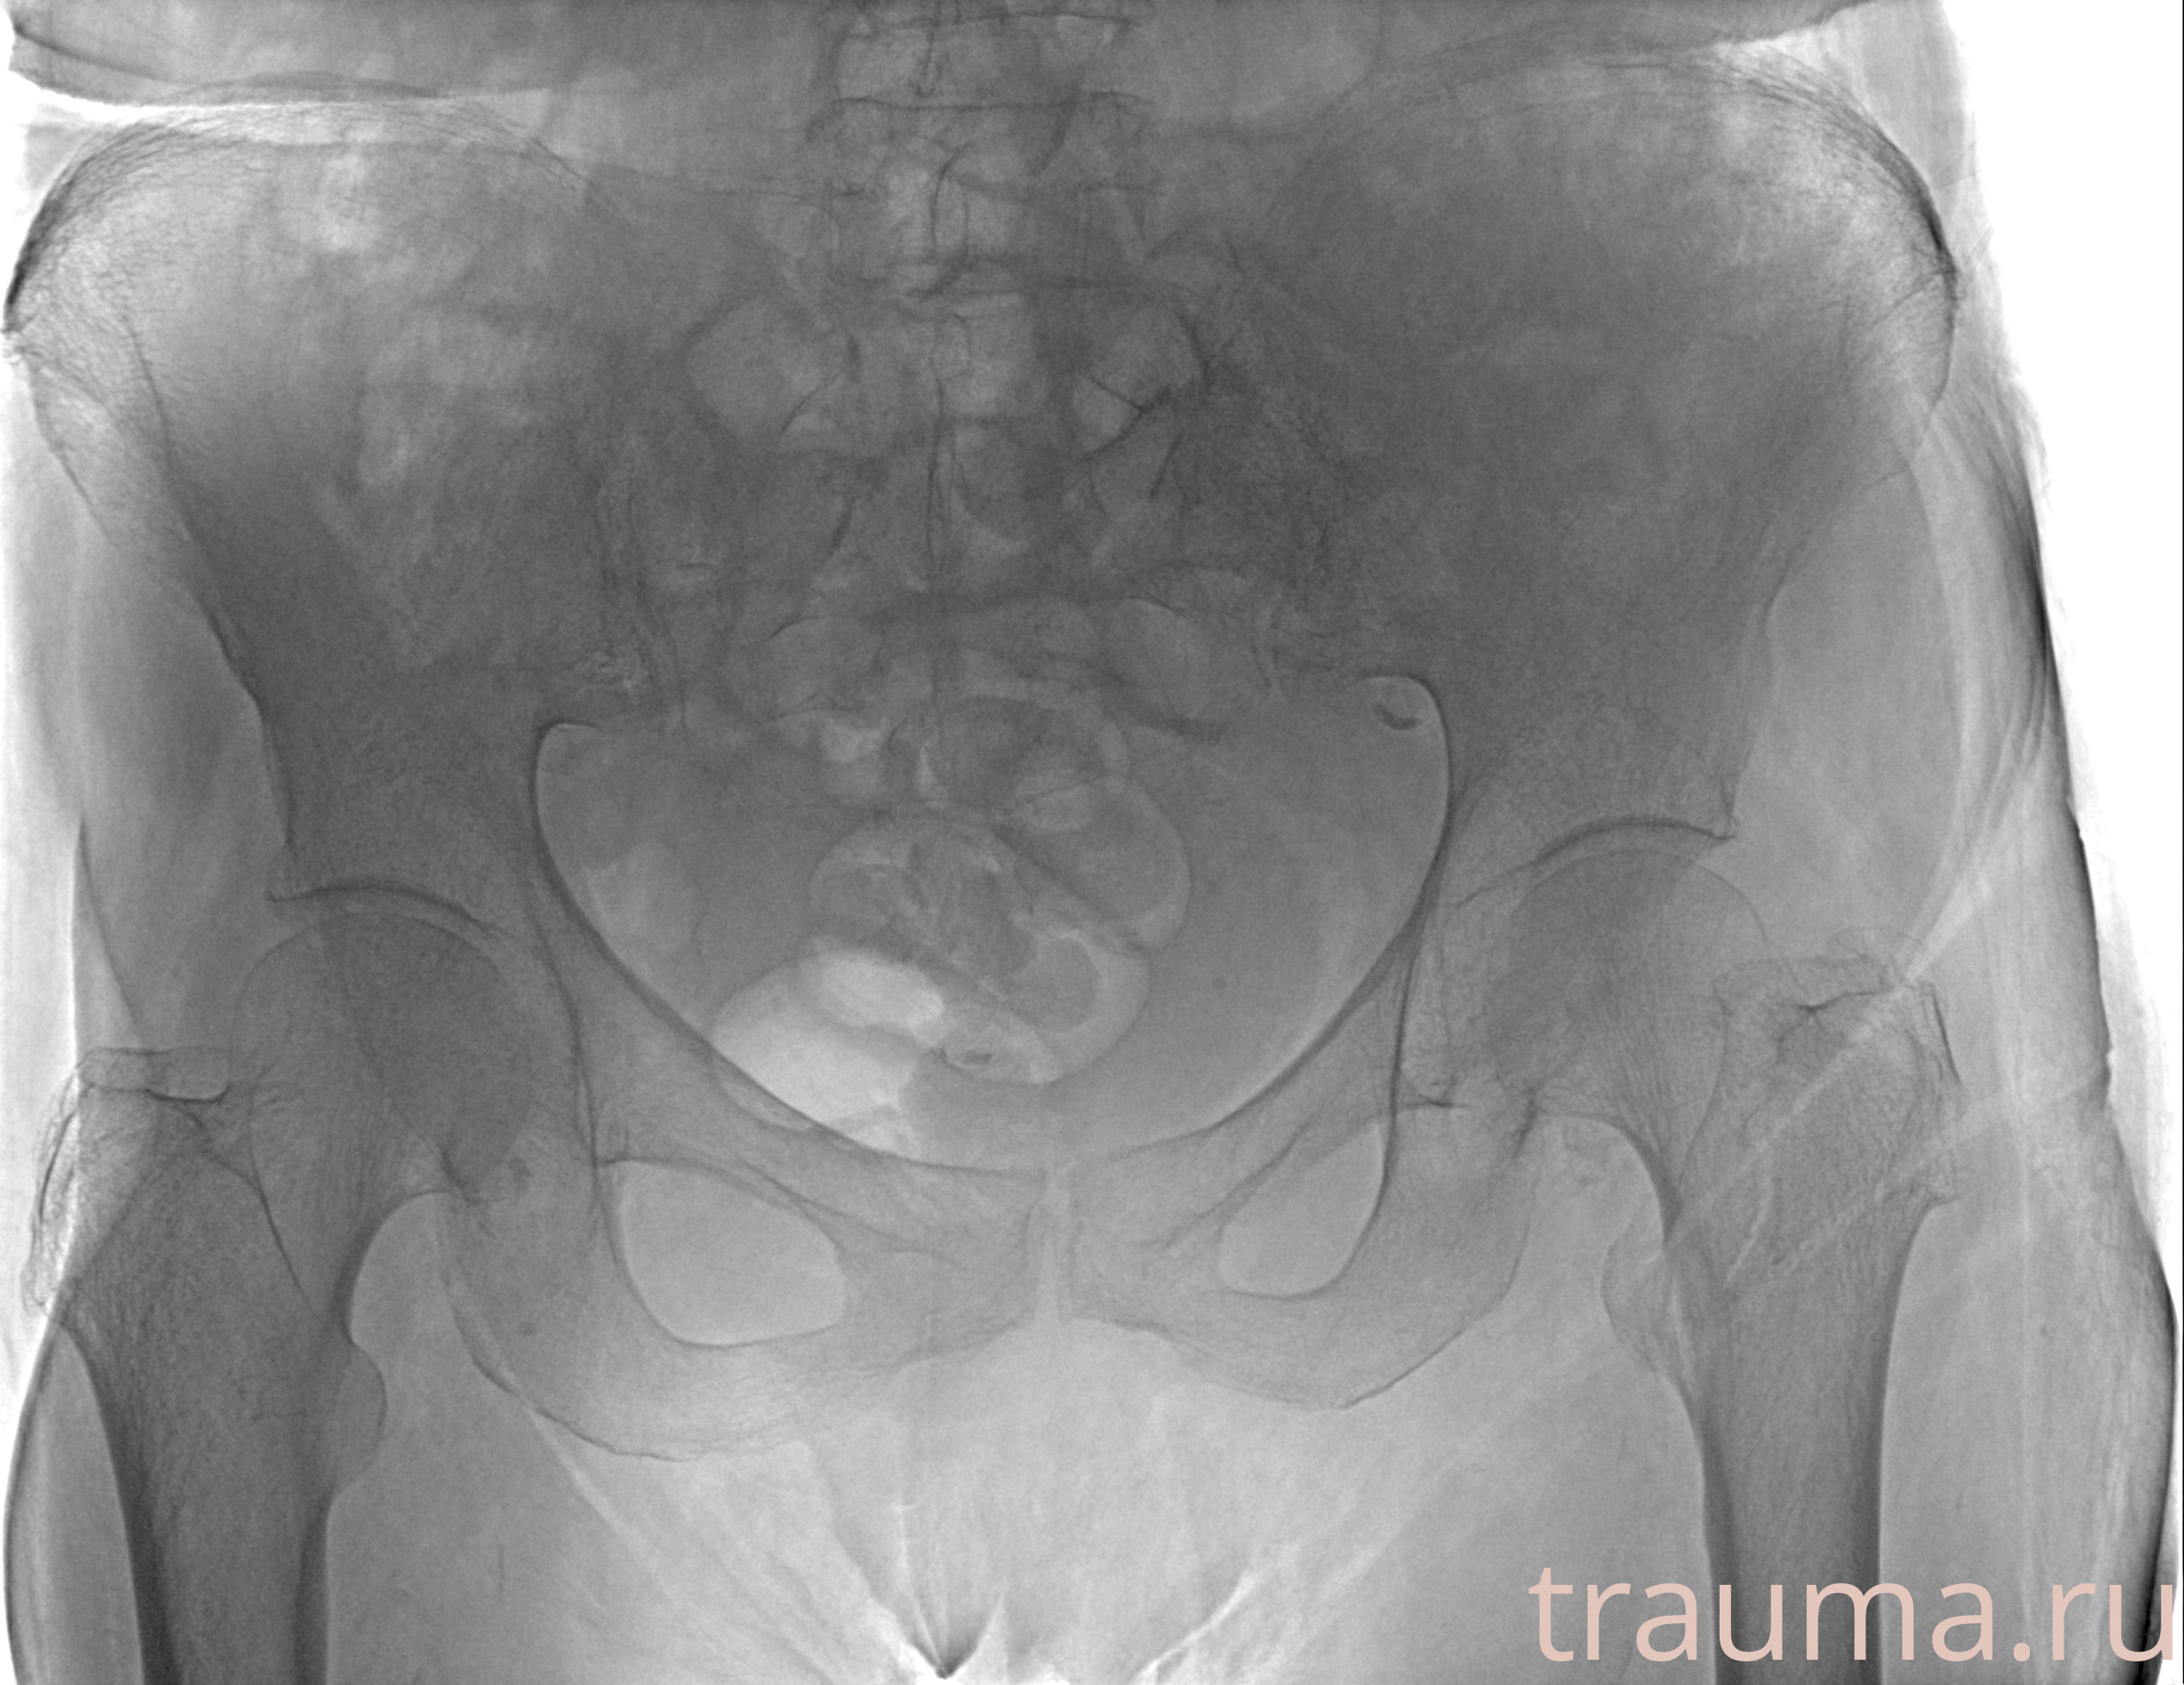

Рентгенограммы

Рентген на дому: по вашему адресу приезжает врач-рентгенолог, травматолог-ортопед с мобильным рентгеновским аппаратом, проводит диагностику травмы или заболевания, делает необходимые рентгенограммы, дает рекомендации по дальнейшему лечению. Получить качественные снимки в домашних условиях возможно благодаря уникальной методике, разработанной МосРентген Центром для института  Склифосовского